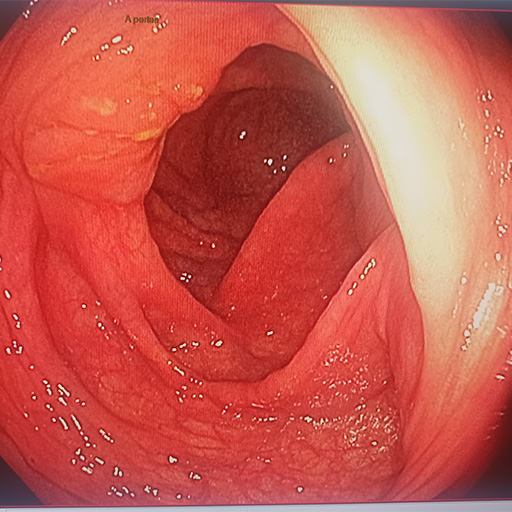

Gastroscopie

Examen de l'œsophage, de l'estomac et du début du duodénum

Coloscopie

Examen du colon, du rectum et de la partie terminale de l'intestin grêle